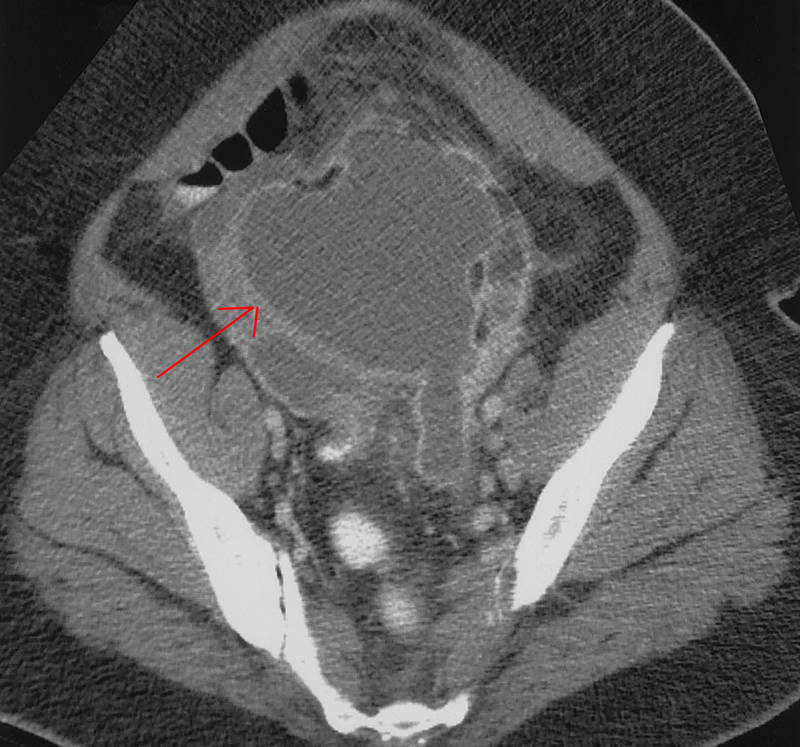

КТ-исследование абсцесса малого таза: Визуализация и диагностика

Раздел: Фотоальбом решений